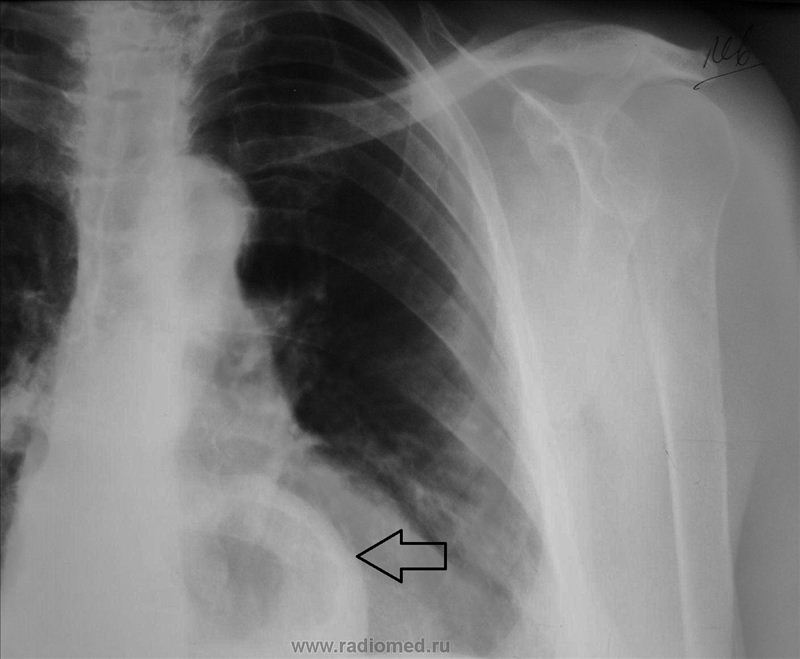

Медицина и диагностика: Аномалии ребер на рентгене